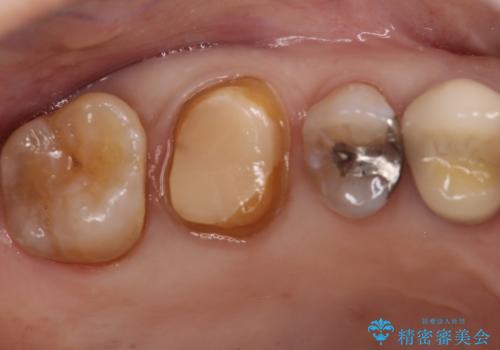

- 他院で入れたセラミックインレーがかけたことを主訴に来院されました。

他の部位にもむし歯を認めたため、優先度の高い歯から治療を行っております。

咬合力が強くかかる部分には欠けるリスクのほとんどない金属を用いることが最良ですが審美性に劣ります。

今回は白い材料での修復を希望されたため、欠けるリスクが高いセラミックインレーは避け、セラミッククラウンにて治療を行いました。